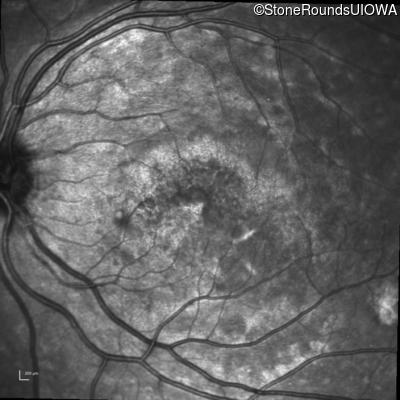

Infrared Fundus Photograph - Right - 20/100 sc

Exemplar